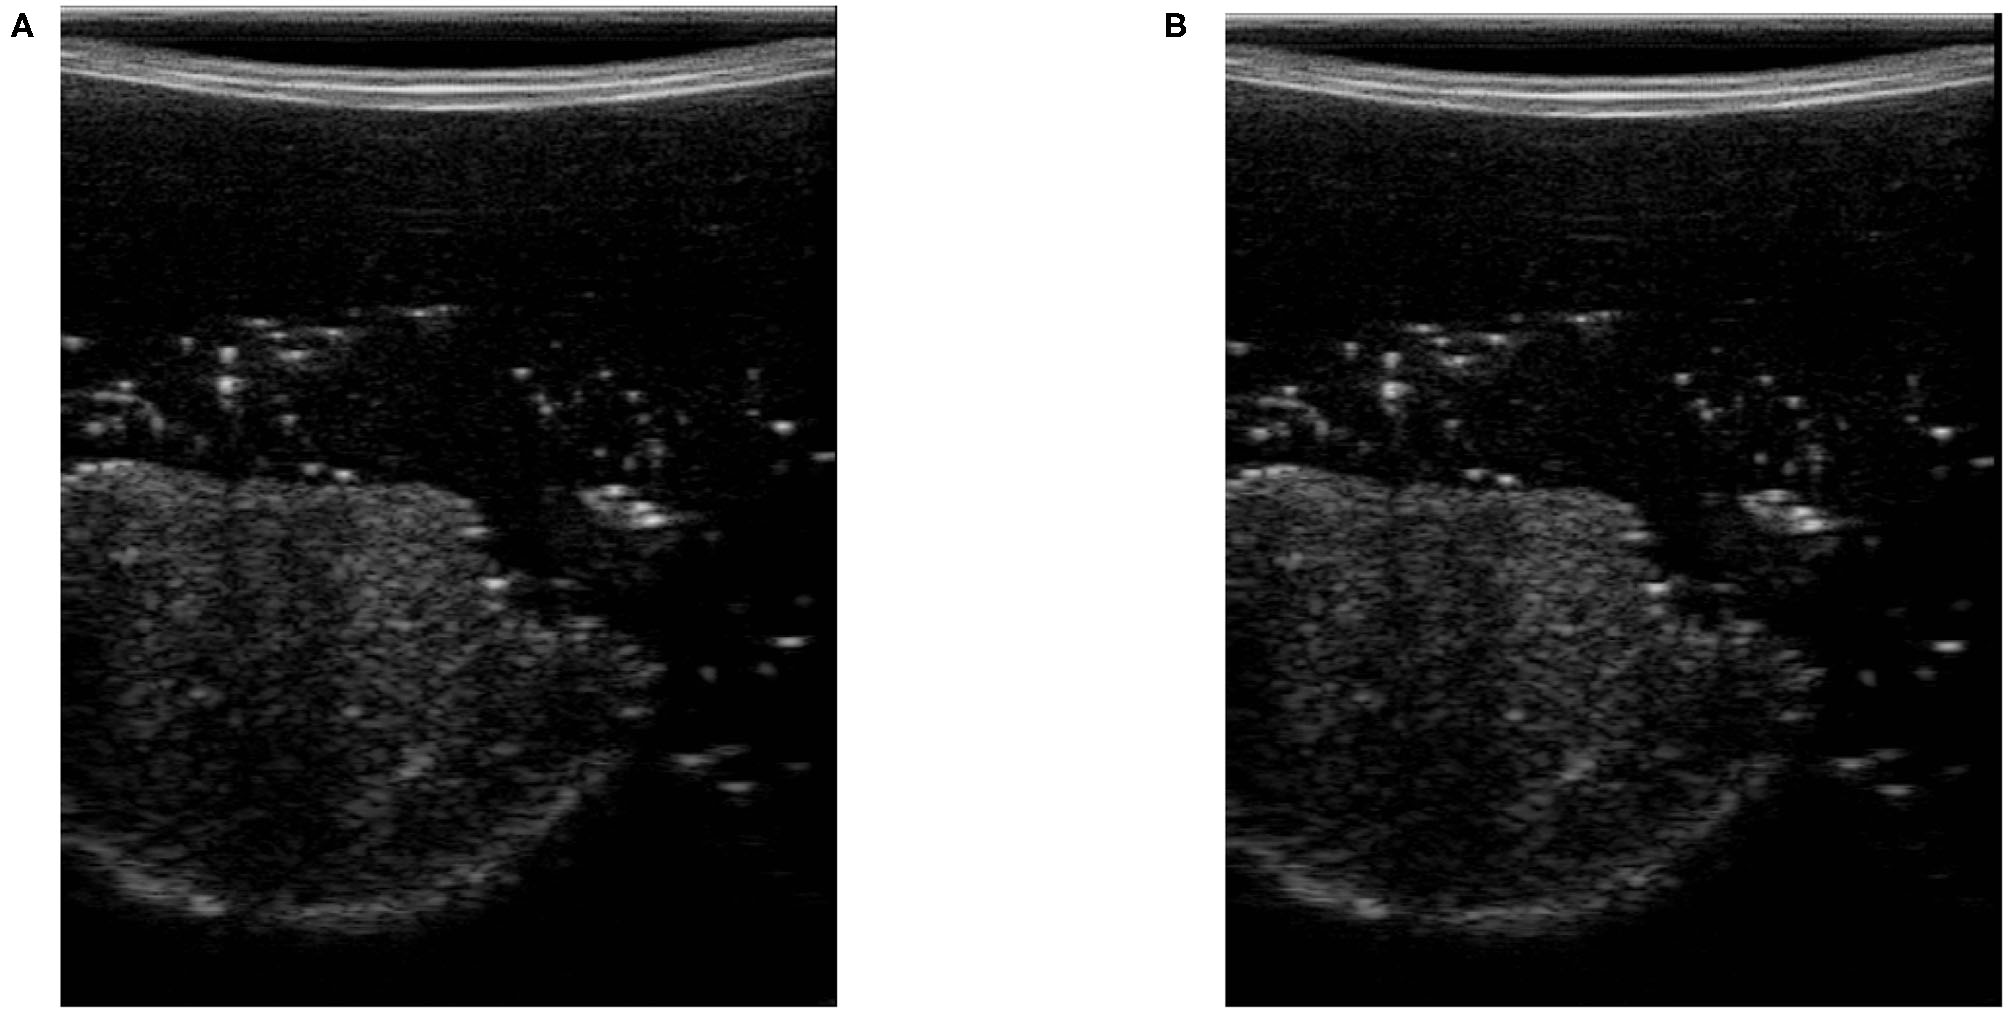

Here, η is the neighborhood with the size of P × Q around each pixel of the noisy image and Ik(px, py) is the intensity of each pixel in the noisy US image. μ is the average of pixel intensity in the original US image, and σ2 is the corresponding variance value in (6). Ik, f(px, py) is the intensity of the US image after removing the noise using Wiener filter and ν2 is the noise variance in the image in (7). Equation (8) finds the difference between US image Ik and filtered image Ik, f to find the US image's noise. In (8), is the average of noise in the image and σn is the corresponding standard deviation value. Figure 5 shows two images with high level (Figure 5A) and low level (Figure 5B) of noise. We have also shown in Figure 6, the variation of the noise feature fn in the US image with respect to measured force FZ|k.

Figure 5

Ultrasound images with high and low levels of noise. (A) Ultrasound image with a high levels of noise. (B) Ultrasound image with a low levels of noise.